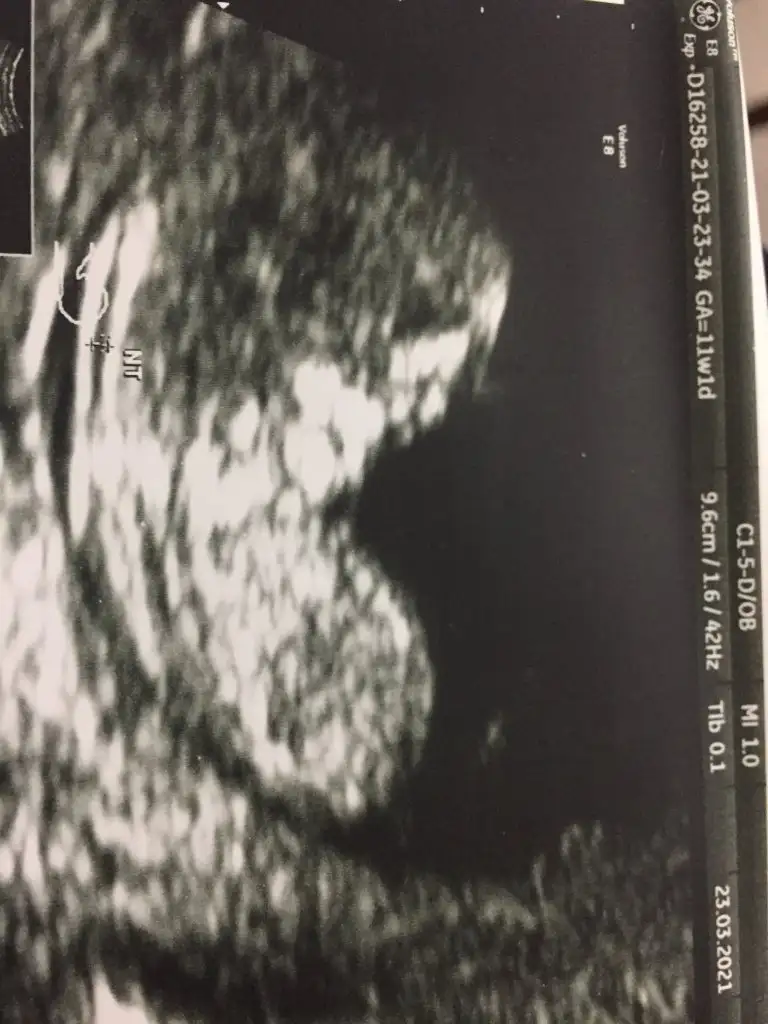

Merhaba canım ilk bebegimi doğru tahmin etmiştim ikinciye hamile kaldım şimdilik bı tane resim var telefonumda ekrandan çekmiştim çıktısı yanımda değil bı bakabilirmisin cinsiyeti acaba ne.9+5burda.

• IMG_20210326_092231.webp

IMG_20210326_092231.webp

53,2 KB · Görüntüleme: 77